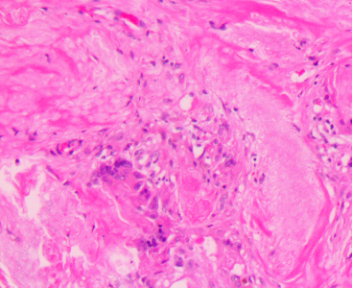

上臂肿物

标本名称

大体所见

灰白不规则软组织1块1.5x1.5x1cm。

图2